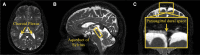

One of the pathological hallmarks of Alzheimer's and related diseases is the increased accumulation of protein amyloid-β in the brain parenchyma. As such, recent studies have focused on characterizing protein and related clearance pathways involving perivascular flow of neurofluids, but human studies of these pathways are limited owing to limited methods for evaluating neurofluid circulation non-invasively in vivo. Here, we utilize non-invasive MRI methods to explore surrogate measures of CSF production, bulk flow and egress in the context of independent PET measures of amyloid-β accumulation in older adults. Participants (N = 23) were scanned at 3.0 T with 3D T2-weighted turbo spin echo, 2D perfusion-weighted pseudo-continuous arterial spin labelling and phase-contrast angiography to quantify parasagittal dural space volume, choroid plexus perfusion and net CSF flow through the aqueduct of Sylvius, respectively. All participants also underwent dynamic PET imaging with amyloid-β tracer 11C-Pittsburgh Compound B to quantify global cerebral amyloid-β accumulation. Spearman's correlation analyses revealed a significant relationship between global amyloid-β accumulation and parasagittal dural space volume (rho = 0.529, P = 0.010), specifically in the frontal (rho = 0.527, P = 0.010) and parietal (rho = 0.616, P = 0.002) subsegments. No relationships were observed between amyloid-β and choroid plexus perfusion nor net CSF flow. Findings suggest that parasagittal dural space hypertrophy, and its possible role in CSF-mediated clearance, may be closely related to global amyloid-β accumulation. These findings are discussed in the context of our growing understanding of the physiological mechanisms of amyloid-β aggregation and clearance via neurofluids.